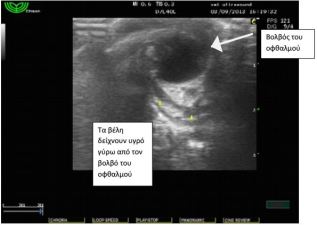

Έγινε υπέρηχος όπου διαπιστώθηκε συγκέντρωση υγρού

αυξημένης ηχογένειας στη περιοχή πίσω από το δεξιό οφθαλμό,

εικόνα συμβατή με οπισθοβολβικό απόστημα. Η αλλοίωση